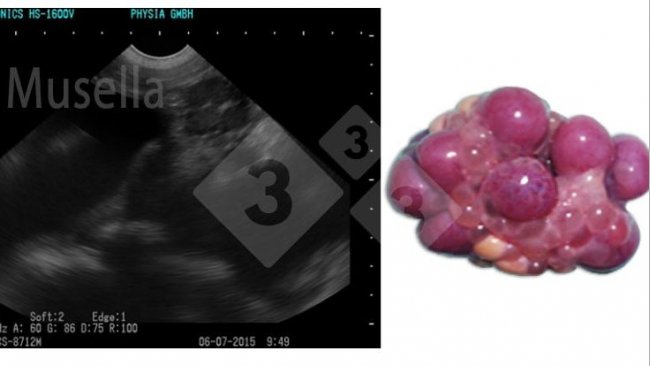

Đây là cách siêu âm có thể được sử dụng để thấy được cấu trúc buồng trứng, đánh giá tình trạng dậy thì và chẩn đoán các bệnh lý buồng trứng.